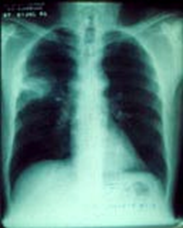

La siguiente es la microscopía de una muestra obtenida de

una masa pulmonar. Con base en las imágenes, ¿Cuál sería el diagnóstico?